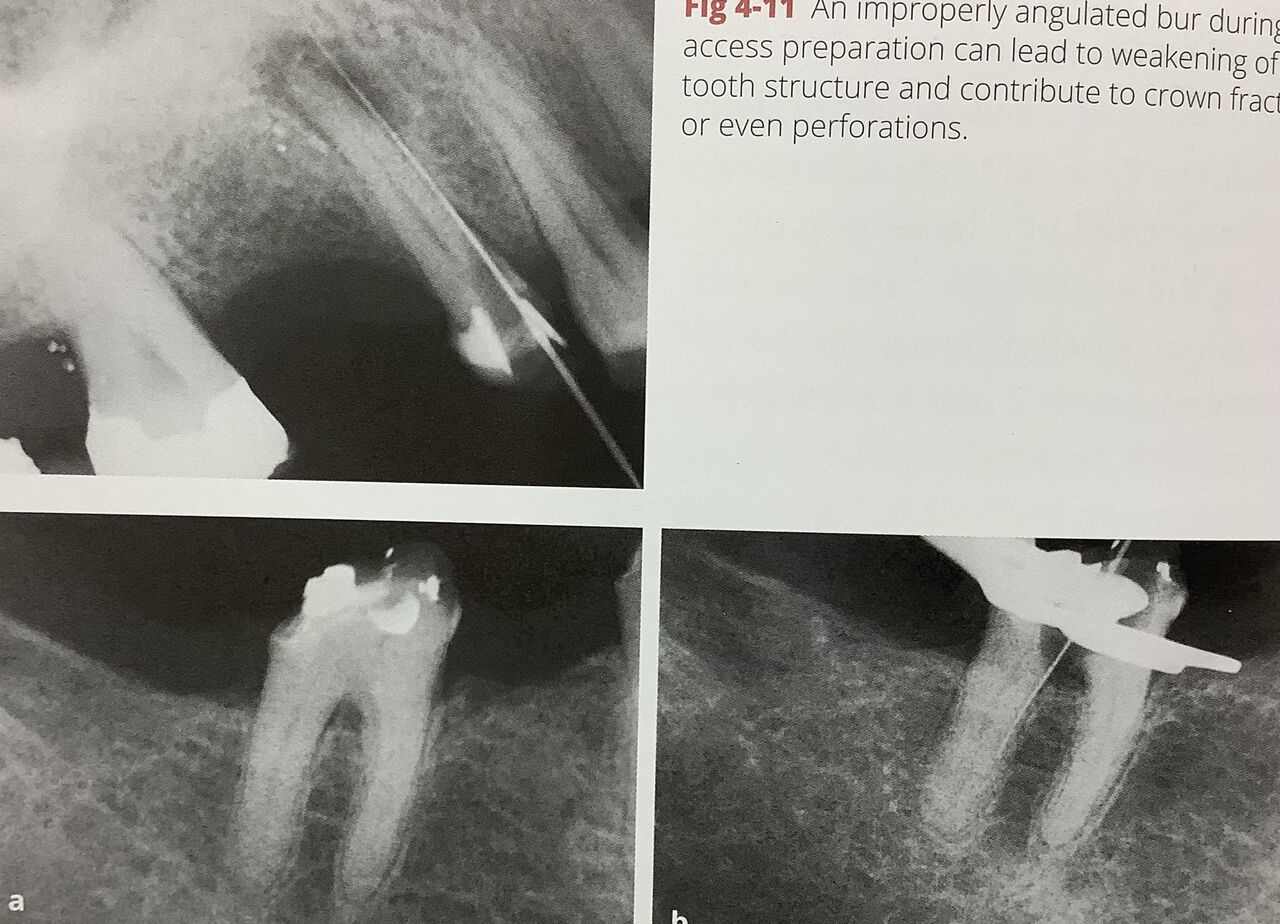

⚫︎歯の長軸、方向と平行に向けて削ります。

向きを間違えると、薄く弱くなったり、穴を開けてしまいます。